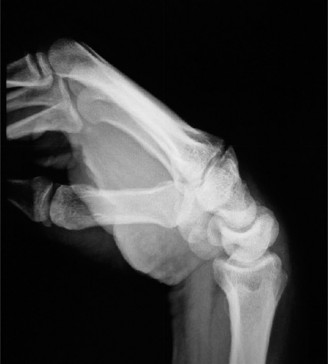

Use 1-2ICSRA to revascularize the scaphoid? CASE 3 ### A patient is brought into the emergency room following a motor vehicle accident. He complains of severe pain in his wrist. Physical examination reveals a tender and swollen wrist. X-rays (Figs. 3–5A–B) are as follows. What is your diagnosis?

Figure 3–5 A–B. (©) Sunil Thirkannad and Christine M. Kleinert.

The correct answer is (D). This x-ray reveals a perilunate injury of the wrist. It is important to be aware of the various radiological parameters that reveal disruption of carpal alignment. Literature suggests that a perilunate injury is missed as much as 25% to 40% of the times. Which radiological signs of perilunate injury can be seen on the above Figs. 3–5A–B .

The correct answer is (E). All three radiological signs are seen on this x-ray. Triangle sign refers to the shape of the lunate seen on the PA view. A normal, well located lunate looks like a tilted trapezium. A triangular-shaped lunate suggests that it is in a hyperflexed position. In the lateral view, a subluxated and volar-tilted lunate has the appearance of a “spilt teacup.” In the above x-ray, Gilula’s first and second lines are broken.